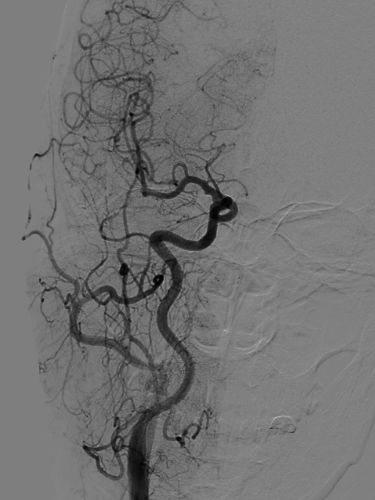

全脑DSA正侧位造影示血流通畅。

动脉瘤内造影剂滞留,未填弹簧圈。行Xper CT,观察见支架完全打开,贴壁良好。术程顺利结束。